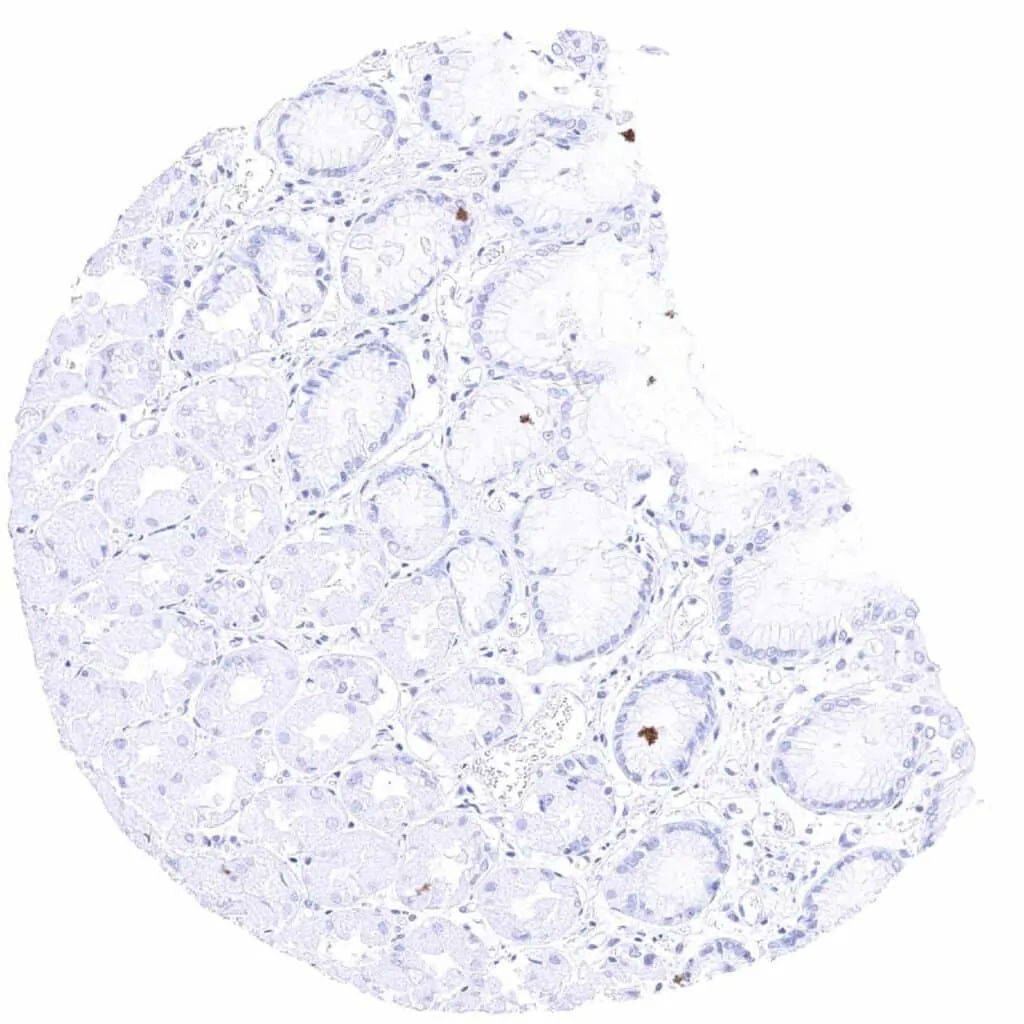

Appendix, mucosa